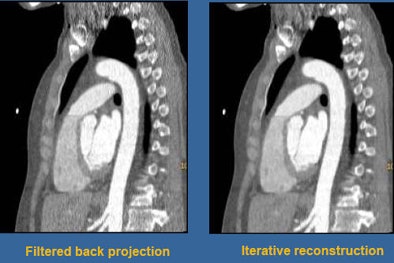

![]() |

| Photon starvation in the shoulder region was even more pronounced when the mAs and kV were reduced in the second study; fortunately, iterative reconstruction brought out a large amount of image detail. |

Using iterative reconstruction, "we cleaned things up a little bit through the body," Halliburton said. "What's impressive is the way we were able to clean things up through the shoulders. I think the use of iterative reconstruction for these really low-dose techniques is enabling us to deal with the shoulder issue."